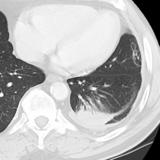

Rounded atelectasis case 1